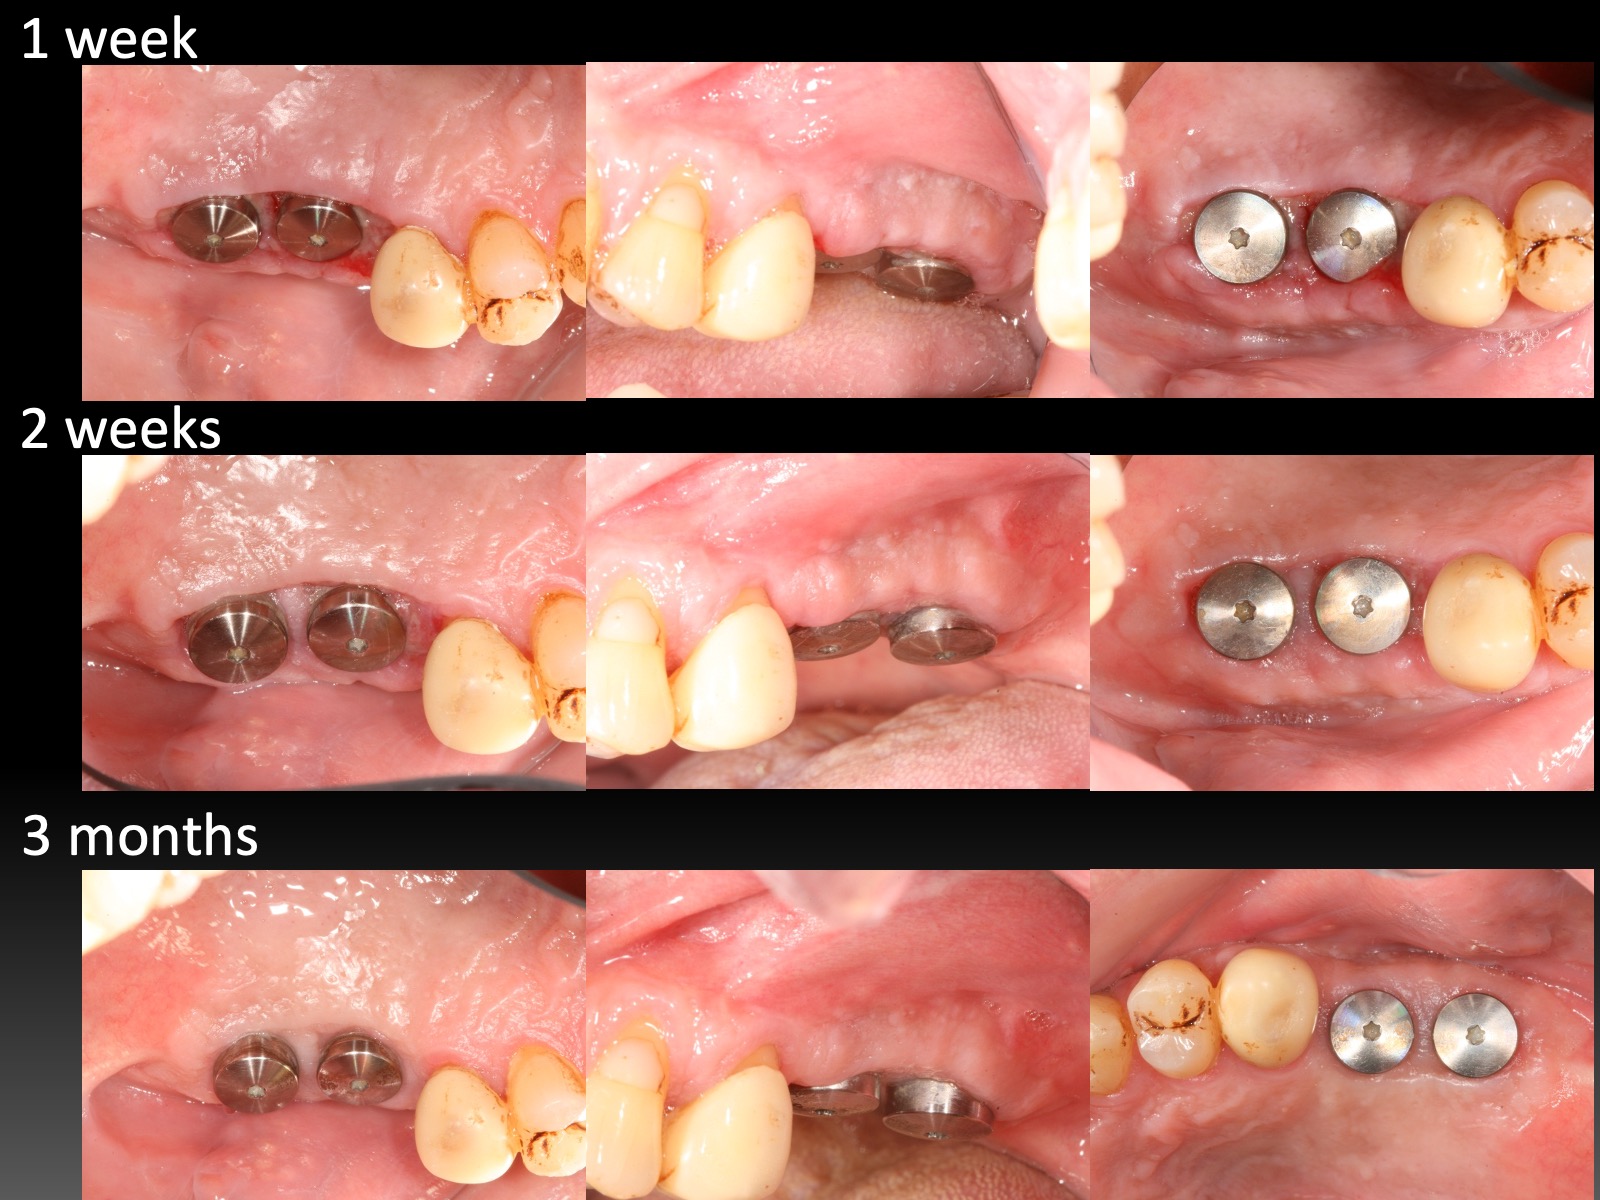

長期追蹤觀察:增加植體角化上皮 Long-term Follow Up of Increase Keratinized Mucosa Around Implant

因為幫學會上課,藉由這次機會,整理了五個長期案例,至少八年到十二年的追蹤。觀察照片,移植角化上皮,經過長年觀察,粗略估計,一年後就很穩定,且多年後,萎縮量沒有很多,蠻平穩的。

以前台大老師有提過,時間久了,可能會因為肌肉層附連拉扯,即使補的寬度多很多,前後MGJ的連線還是會呈現一直線,原有多補的會縮一些回去。不過,我自己的案例,例如Case D,經過九年後,角化上皮還是很寬,呈現前後連線不是很一致的狀態。有這些發現,其實蠻有意思的~